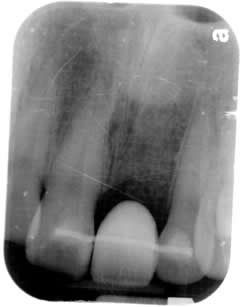

Single Front Tooth Implant :

Feb 2009

Temporary crown is always provided for esthetic concern.